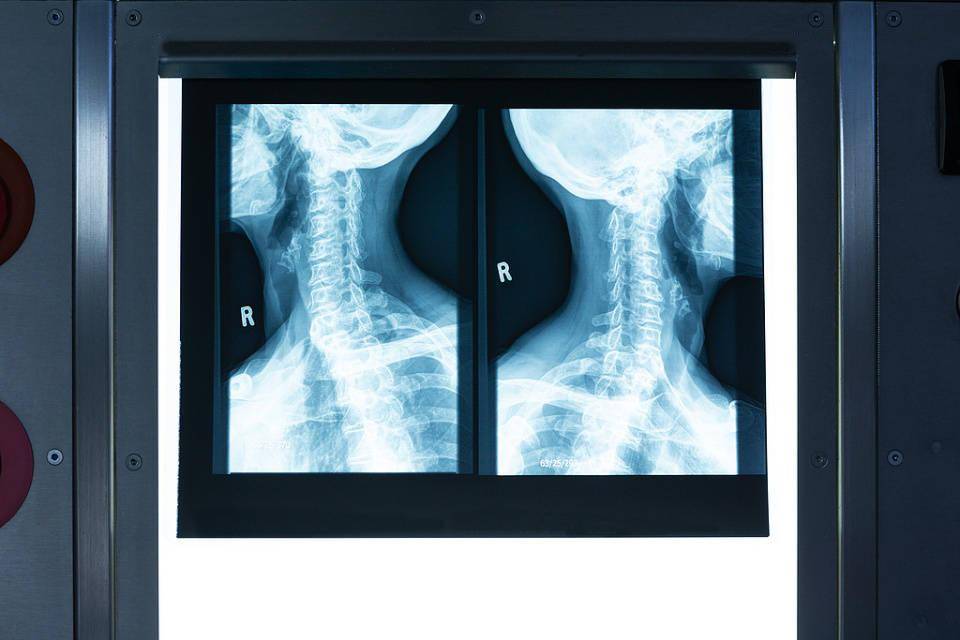

影像学检查中,颈椎磁共振是诊断脊髓型颈椎病的金标准,能清晰显示脊髓受压的部位、程度以及脊髓本身是否有变性改变。颈椎X光片可以看颈椎整体序列、椎间隙高度和骨赘情况,但无法直接观察脊髓受压。CT检查对于判断韧带骨化有参考价值。